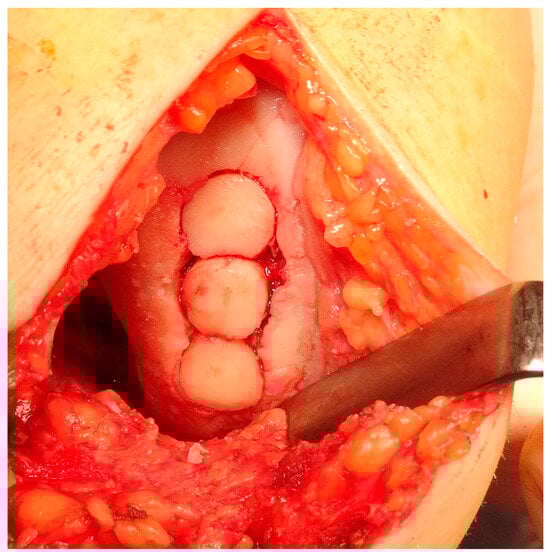

Osteochondral autograft transplantation (OAT) involves the transplantation of grafts obtained from the non-weight-bearing areas of the joint to the injured regions that bear more weight []. The application of autograft results in a more expedited and dependable process of osseous integration compared to the osteochondral allograft. Furthermore, the autograft presents several advantages, including convenient accessibility to donor cartilage, capacity for addressing lesions of different sizes, and utilization of the native hyaline cartilage containing functional and fully developed chondrocytes [,]. Good results of OATS have been described for small defects (<2 cm2), but larger defects ranging from 2 to 4 cm2 can also be treated beneficially with this method, especially in young, demanding patients []. This technique is the first line of treatment for cartilage lesions involving the subchondral layer []. The histologic examination of the transplanted osteochondral graft has revealed that in an ideal OATS, the grafts are successfully integrated into the defects to preserve the structural integrity of the hyaline cartilage and cancellous bone. This integration also ensures the maintenance of a smooth and congruent articular surface in the weight-bearing regions [,]. Intraoperative views of the OATS procedure are shown in Figure 8 and Figure 9.

Figure 8.

Intraoperative view of donor site preparation for osteochondral blocks implantation on the lateral femoral condyle.

Figure 9.

Intraoperative view of the final result with complete cartilage loss area coverage.